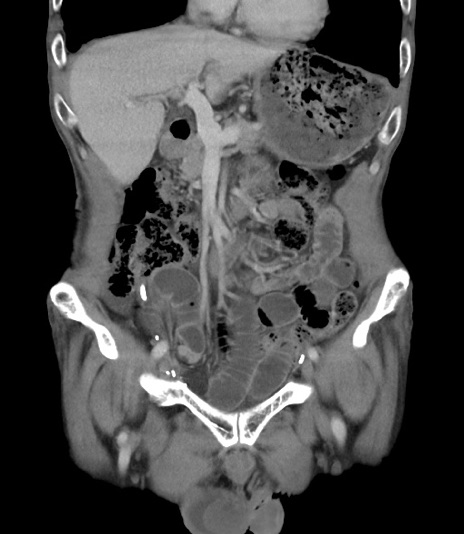

症例3(冠状断像)

【症例】 70歳代男性

【主訴】右鼠径部腫瘤、疼痛

【現病歴】本日朝より上記主訴あり、受診。

【既往歴】膀胱癌にて膀胱全摘、両側尿管皮膚瘻

【データ】WBC 5600、CRP 0.56